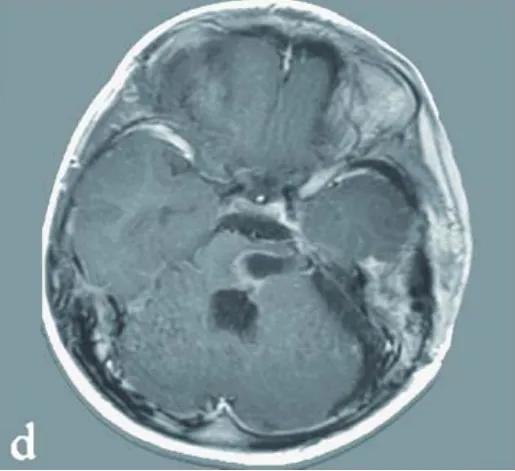

面瘫、斜视、偏瘫,脑桥海绵状血管瘤手术为何步步惊心?

脑干脑桥海绵状血管瘤一旦出血,后果不堪设想。手术切除是根治病灶的希望所在。然而,手术风险极高,稍有不慎便可能伤及重要神经,如何选择最安全的手术入路,是神经外科领域持续探索...